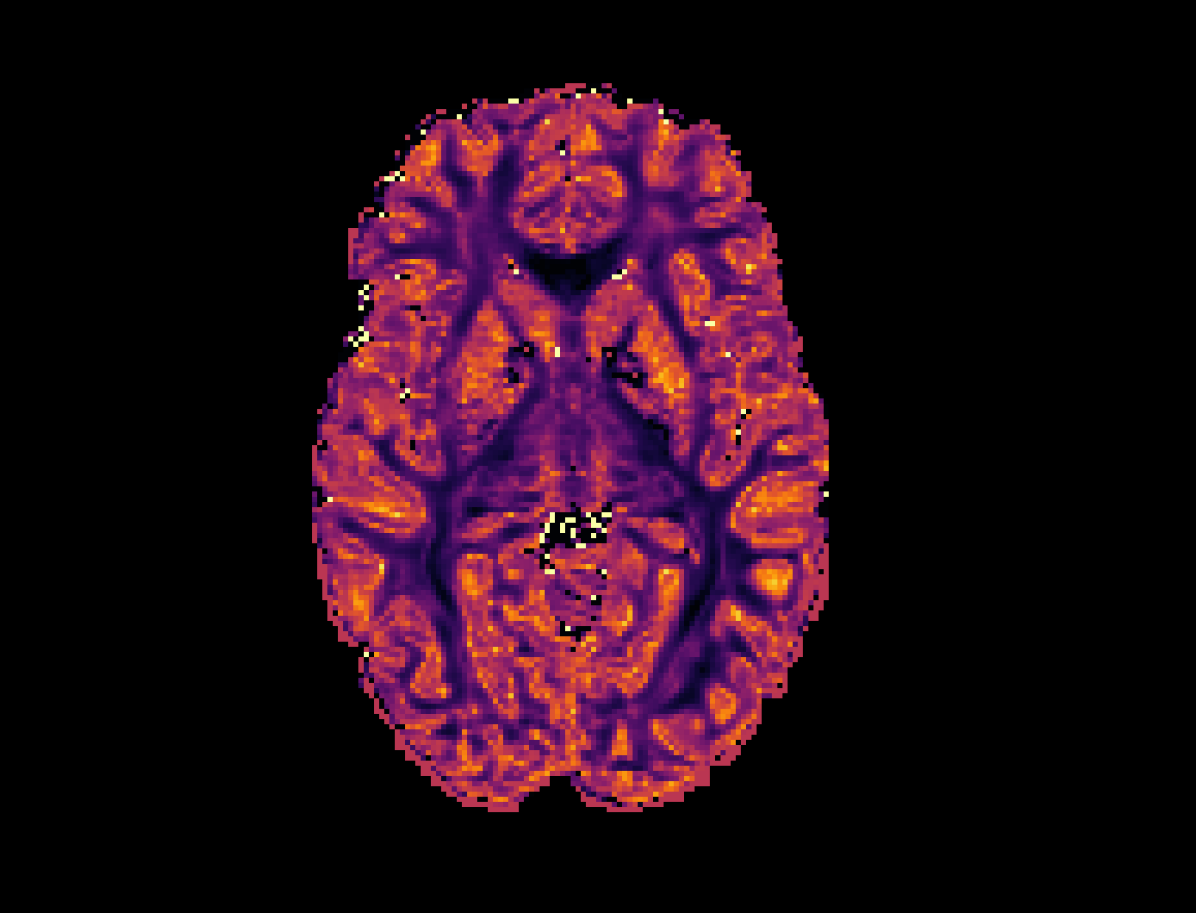

Refer to caption

Figure 1: Visualisation of dMRI parametric continuous convolution. Points 𝐱isubscript𝐱𝑖\mathbf{x}_{i} and 𝐲jsubscript𝐲𝑗\mathbf{y}_{j} are of the form (u,v,w,ρ,ϑ,φ)superscript𝑢𝑣𝑤𝜌italic-ϑ𝜑top(u,v,w,\rho,\vartheta,\varphi)^{\top} with spatial components (u,v,w)𝑢𝑣𝑤(u,v,w) and angular components (ρ,ϑ,φ)𝜌italic-ϑ𝜑(\rho,\vartheta,\varphi). Left: The raw dMRI data f(𝐱)𝑓𝐱f(\mathbf{x}). Points 𝐱4subscript𝐱4\mathbf{x}_{4} and 𝐱6subscript𝐱6\mathbf{x}_{6} are located in the same region on the q-space sphere and thus have the same angular components. Similarly, 𝐱6subscript𝐱6\mathbf{x}_{6} and 𝐱20subscript𝐱20\mathbf{x}_{20} have the same spatial coordinates but different angular components. Middle: the parametric continuous kernel, whose geometry is defined by the coordinate embedding 𝐞𝐞\mathbf{e}. Right: Sampled points from q-space are pointwise multiplied with the kernel and summed over to produce one output feature h(𝐲j)subscript𝐲𝑗h(\mathbf{y}_{j}).

We define q-space \mathbb{Q} as the joint spatial-angular domain within dMRI where ={(u,v,w,ρ,ϑ,φ)u,v,w,ρ,0ϑ<2π,0φπ}conditional-setsuperscript𝑢𝑣𝑤𝜌italic-ϑ𝜑topformulae-sequence𝑢𝑣𝑤𝜌0italic-ϑ2𝜋0𝜑𝜋\mathbb{Q}=\{(u,v,w,\rho,\vartheta,\varphi)^{\top}\mid u,v,w,\rho\in\mathbb{R},0\leq\vartheta<2\pi,0\leq\varphi\leq\pi\} and 𝐱j,𝐲isubscript𝐱𝑗subscript𝐲𝑖\mathbf{x}_{j},\mathbf{y}_{i}\in\mathbb{Q}. Here, (u,v,w)superscript𝑢𝑣𝑤top(u,v,w)^{\top} denote the spatial components, and (ρ,ϑ,φ)superscript𝜌italic-ϑ𝜑top(\rho,\vartheta,\varphi)^{\top} denote the angular components. Specifically, ϑitalic-ϑ\vartheta and φ𝜑\varphi refer to the azimuthal and polar angles, respectively, which form the set of points on the surface of a sphere of radius ρ𝜌\rho. In this context, ρ𝜌\rho is the diffusion weighting or b-value. Figure 1 visualises convolutions across q-space through Equation (2). To perform convolutions using q-space, we first calculate a coordinate embedding 𝐞2LE𝐞superscript2𝐿𝐸\mathbf{e}\in\mathbb{R}^{2LE} via

Here pmsubscript𝑝𝑚p_{m} is the m𝑚mth component of the coordinate vector 𝐩E𝐩superscript𝐸\mathbf{p}\in\mathbb{R}^{E} given by 𝐩=[uiuj,vivj,wiwj,ρiρj,dr]𝐩subscript𝑢𝑖subscript𝑢𝑗subscript𝑣𝑖subscript𝑣𝑗subscript𝑤𝑖subscript𝑤𝑗subscript𝜌𝑖subscript𝜌𝑗subscript𝑑𝑟\mathbf{p}=[u_{i}-u_{j},v_{i}-v_{j},w_{i}-w_{j},\rho_{i}-\rho_{j},d_{r}]. We have opted to enforce rotational invariance across the sphere by omitting ϑitalic-ϑ\vartheta and φ𝜑\varphi directly, and instead use p5=dr(ϑj,φj,ϑi,φi)subscript𝑝5subscript𝑑𝑟subscriptitalic-ϑ𝑗subscript𝜑𝑗subscriptitalic-ϑ𝑖subscript𝜑𝑖p_{5}=d_{r}(\vartheta_{j},\varphi_{j},\vartheta_{i},\varphi_{i}) where dr(ϑj,φj,ϑi,φi)=sin(ϑj)sin(ϑi)+cos(ϑj)cos(ϑi)cos(φjφi)subscript𝑑𝑟subscriptitalic-ϑ𝑗subscript𝜑𝑗subscriptitalic-ϑ𝑖subscript𝜑𝑖subscriptitalic-ϑ𝑗subscriptitalic-ϑ𝑖subscriptitalic-ϑ𝑗subscriptitalic-ϑ𝑖subscript𝜑𝑗subscript𝜑𝑖d_{r}(\vartheta_{j},\varphi_{j},\vartheta_{i},\varphi_{i})=\sin(\vartheta_{j})\sin(\vartheta_{i})+\cos(\vartheta_{j})\cos(\vartheta_{i})\cos(\varphi_{j}-\varphi_{i}). The function γ:2L:𝛾superscript2𝐿\gamma:\mathbb{R}\rightarrow\mathbb{R}^{2L} is a Fourier feature mapping motivated by Tancik et al. [35] and Mildenhall et al. [27] which is used to improve the hypernetwork’s ability to learn high-frequency functions. In practice, L𝐿L is a hyperparameter of the PCConv layer. Figure 2 provides examples of weights sampled from a trained PCConv layer with varying drsubscript𝑑𝑟d_{r}. The channels selected within the Figure demonstrate a variety of functions across the sphere, highlighting the network’s ability to learn both high and low frequency kernels.